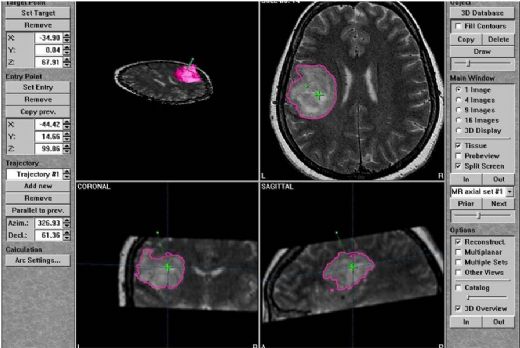

Stereotaktik Biyopsi Nasıl Yapılır? Stereotaktik biyopsi işlemi, birkaç aşamadan oluşur:

Stereotaktik biyopsi, genellikle meme veya beyin gibi vücut bölgelerindeki anormal dokuların incelenmesi amacıyla kullanılan, görüntüleme teknikleri ile rehberlik edilen bir biyopsi yöntemidir. Bu işlem, hedeflenen bölgeye doğru hassas bir şekilde iğne ile örnek almak için kullanılır.

Stereotaktik biyopsi geçirmiş bir hasta olarak, bu işlemin ne kadar önemli ve etkili olduğunu düşünmeden edemiyorum. Özellikle, beynimdeki bir kütlenin kesin tanısını öğrenmek için bu yöntemin kullanılması beni oldukça rahatlattı. Ameliyat öncesi süreçte, stereotaktik çerçeve takılması ve MR ile doğru yerin belirlenmesi oldukça dikkatli bir şekilde yapıldı. Ameliyat sırasında lokal anestezi kullanılması, sürecin daha az rahatsız edici olmasına yardımcı oldu. Tam on dakika süren bir işlem, aslında hayatımda büyük bir fark yaratacak bir tanı almak için oldukça kısa bir süre. Sonrasında yaşanan baş ağrısı ve rahatsızlık hissi, beklediğim bir durumdu ama bunun geçici olduğunu bilmek içimi rahatlattı. Stereotaktik biyopsinin minimal invaziv olması ve komplikasyon riskinin düşük olması, bu yöntemi tercih etmemdeki en büyük etkenlerden biriydi. Ameliyat sonrası bakımın ne kadar önemli olduğu konusunda dikkatli olmaya çalışıyorum. Başımı yüksek tutmak, ağrı kesicileri doktorun önerdiği gibi almak ve kontrolleri aksatmamak, iyileşme sürecimi hızlandıracak gibi görünüyor. Sonuçların iki-üç gün içinde geleceği bilgisi, beni biraz gerse de, bu sürecin sonunda sağlığım hakkında doğru bilgiye ulaşmak için sabırlı olmam gerektiğini biliyorum. Stereotaktik biyopsi, beynimdeki hastalıklı bölgeden doğru örnek alarak doğru bir tanı koyma şansını artırdı ve bu süreçteki deneyimlerim benim için oldukça kıymetli.